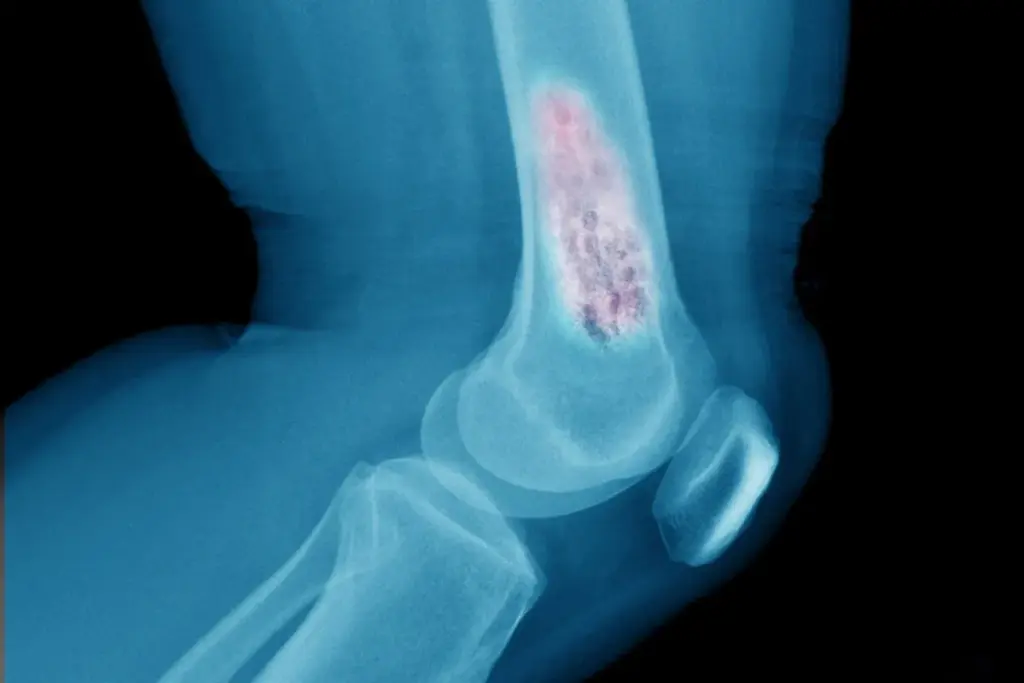

The initial evaluation begins with advanced cross-sectional imaging. For soft tissue masses of the extremities or trunk, Magnetic Resonance Imaging (MRI) is the gold standard. MRI provides exquisite soft-tissue contrast, allowing the radiologist to distinguish the tumor from surrounding muscle, fat, and edema. It is critical to define the “compartment” of the cancer—whether it is contained within a specific muscle group or has breached the fascial barriers. For bone sarcomas, plain radiographs (X-rays) provide the first clue, revealing characteristic patterns of bone destruction (osteolysis) and new bone formation (osteoid). An MRI follows this to assess the extent of the tumor within the marrow space and any soft tissue extension.

• Computed Tomography of the chest is mandatory for all sarcoma patients to rule out pulmonary metastases, the most common site of spread.

• Positron Emission Tomography scans use radiolabeled glucose to assess tumor metabolic activity, helping distinguish necrosis from active disease.